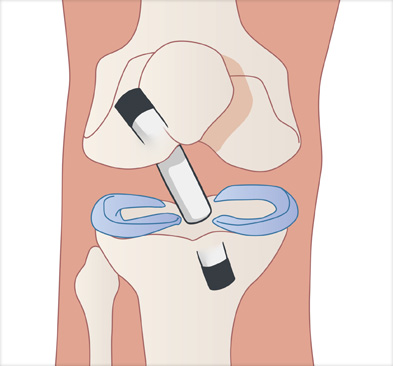

이식할 인대 삽입

십자인대 재건술은 손상된 인대를 자가건이나 타가건을 활용해 원래의 인대의 위치에 재건하여 무릎의 기능을 회복시킵니다.